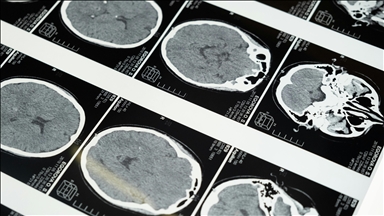

Çok yorulan ve efor sarf eden epilepsi hastası çocukların yaşam kalitesinin daha sık nöbet geçirmeleri nedeniyle düşebileceği bildirildi.

Cumhuriyet Üniversitesi (CÜ) Tıp Fakültesi Nöroloji Ana Bilim Dalı Öğretim Üyesi Prof. Dr. Ertuğrul Bolayır, AA muhabirine yaptığı açıklamada, halk arasında "sara" olarak bilinen epilepsinin genellikle genetiksel olarak ortaya çıktığını söyledi.

Bolayır, özellikle çocukluk çağındaki epilepside yaşam tarzına dikkat edilmesi gerektiğini vurgulayarak, "Çocukluk çağındaki genetik epilepsilerde yaşam tarzı çok önemli. Epilepsi nöbetleri çok efor sarf eden çocuklarda sık görülür. Bu çocukların çok yorulmamaları, fazla spor yapmamaları gerekiyor. Böyle olduğunda yaşam kaliteleri de düşüyor" diye konuştu.